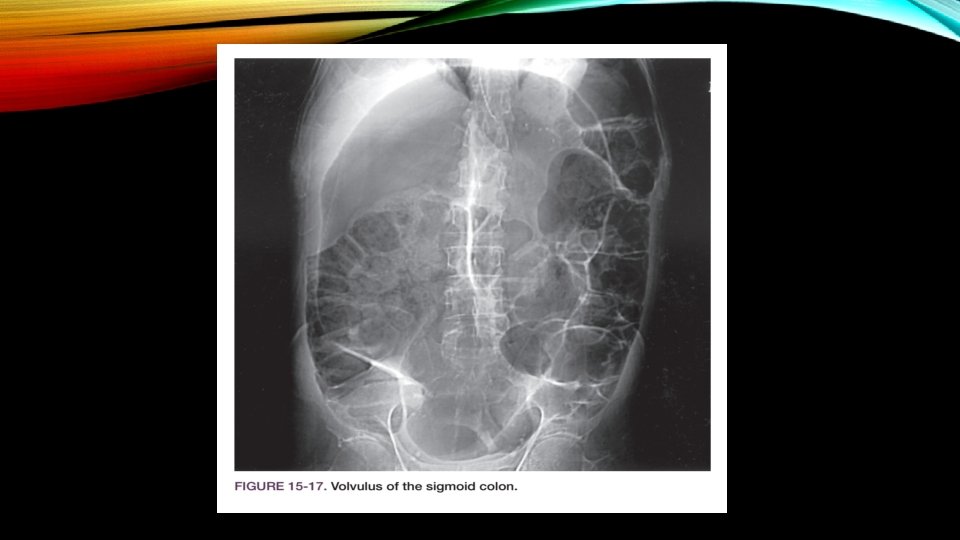

VOLVULUS OF THE LARGE INTESTINE • sigmoid (70%) • cecum (30%) • Volvulus accounts for 5% to 10% of cases of large bowel obstruction • second most common cause of complete colonic obstruction • Stretching and elongation of the sigmoid with age • patients who are confi ned to psychiatric institutions or nursing homes have an increased risk for this disease

CLINICAL PRESENTATION AND EVALUATION • Abdominal distension • Vomiting • Abdominal pain • Obstipation • Tachypnea • Tympany • High-pitched tinkling sounds

DIAGNOSTIC STUDIES • Abdominal x-ray films (kidney bean appearance) • Watersoluble contrast enemas (funnel-like narrowing that often resembles a bird’s beak) • CT scan

TREATMENT • Sigmoidoscopy with rectal tube insertion • Strangulation or Perforation is suspected or if attempts to decompress the bowel are unsuccessful = Emergency operation • Cecal volvulus is always treated surgically, rarely with cecopexy (suturing the cecum to the parietal peritoneum) and most commonly with right hemicolectomy with ileotransverse colostomy